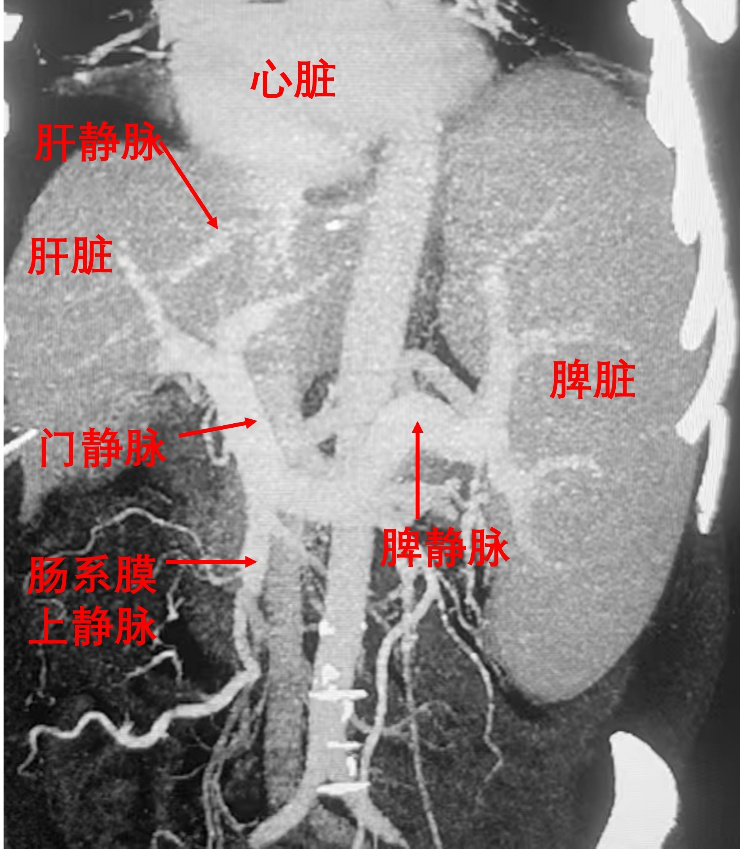

图1.正常肝脏血管解剖。肠系膜上静脉引流肠道血液至肝脏,经肝静脉回流心脏。门静脉狭窄为肝前性门静脉高压,肝静脉狭窄为肝后性门静脉高压。肝脏内病变为肝窦性门静脉高压。各种门静脉高压,导致肠系膜上静脉血液无法流回肝脏,压力升高,可引起腹腔积液、消化道出血等并发症。